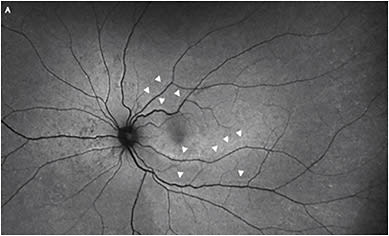

There is also emerging evidence that the integrity of retinal reattachment varies with the surgical technique chosen. A recent study demonstrated that PnR was associated with a greater chance of achieving a high integrity retinal attachment (HIRA) compared with PPV.2 This may be related to several factors, but particularly that PnR is an RPE pump-based procedure where the gas bubble occludes the retinal break and the RPE pump is responsible for slowly achieving retinal reattachment. Furthermore, PnR utilizes a smaller gas bubble, which applies less buoyant force to a smaller area of retina, thereby increasing the chance of HIRA. To the contrary, PPV is associated with a rapid iatrogenic process of retinal reattachment in which fluid is manually removed from the subretinal space over a short period of time. Moreover, large gas fills are used with a large buoyant force applied to a large area of retina, which likely leads to a high risk of retinal displacement or a low integrity retinal attachment (LIRA) (Figure 1).